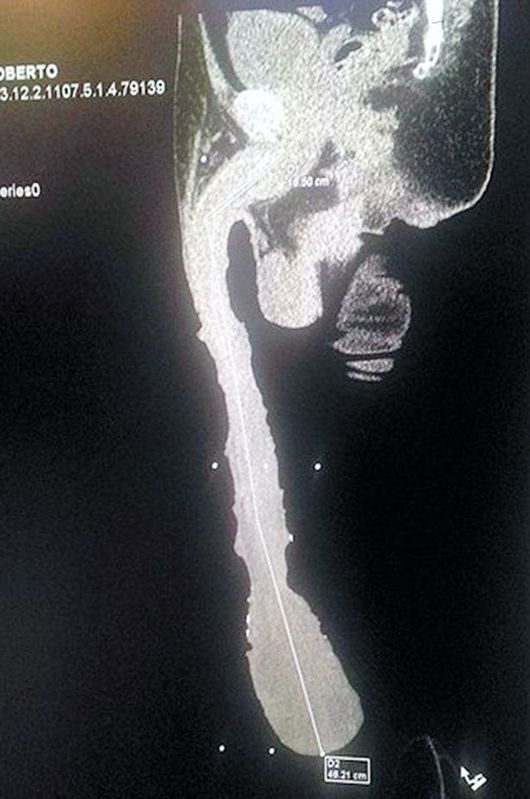

영국 일간지 ‘미러’는 5일(현지시간) 세상에서 가장 긴 성기를 가진 남성의 사연을 소개했다. 주인공은 멕시코의 로베르토 에스퀴벨 카브레라(52)라는 남성. 이 매체에 따르면 카브레라는 길이 18.9인치(약 48cm), 무게 2.2파운드(약 998g)의 거대한 성기를 보유하고 있다.

미러 홈페이지 캡처.